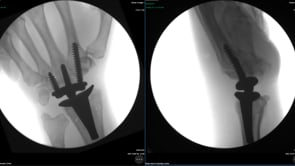

Nuestra paciente buscó durante años un médico que le ofreciera una alternativa para su muñeca rígida. Se negó a conformarse con una artrodesis y acudió al Badia Hand To Shoulder Center para un reemplazo total de muñeca. En este video, a tan solo 6 días de la operación, muestra una excelente flexión y extensión bajo fluoroscopia.